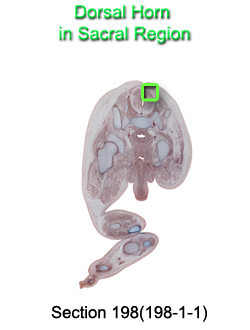

Dorsal Horn in Sacral Region

Carnegie Embryo #9226

198-01-01